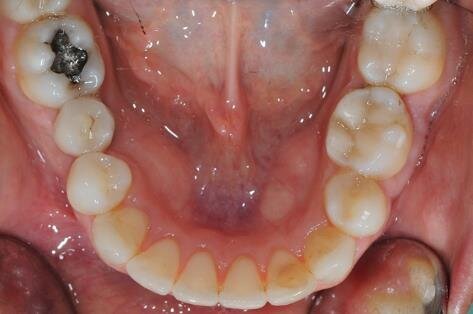

Figg. 2a-2c - Foto intraorali pretrattamento: visioni frontale (a), laterali (b).

All’esame clinico del viso si osservava una sostanziale simmetria bilaterale e corrette proporzioni facciali verticali frontali e laterali (Figg. 1a-1c). Il sorriso presentava un’adeguata esposizione degli incisivi superiori e dei corridoi buccali e la centratura della linea mediana superiore rispetto al volto. All’ispezione del cavo orale, invece, si riscontrava una lieve deviazione della linea mediana inferiore verso destra di circa 1 mm, con contestuale II Classe canina a destra (Figg. 2a-2c). La mancanza del primo molare inferiore di destra aveva prodotto lo spostamento mesiale, la mesio-inclinazione del secondo e terzo molare inferiore e l’estrusione del primo molare superiore. A sinistra, invece, era riscontrabile una I Classe canina e molare. Erano presenti un moderato affollamento nell’arcata superiore ed un lieve disallineamento degli incisivi inferiori. L’overjet era lievemente aumentato e l’arcata superiore appariva lievemente contratta, soprattutto a destra. Erano presenti recessioni gengivali multiple.